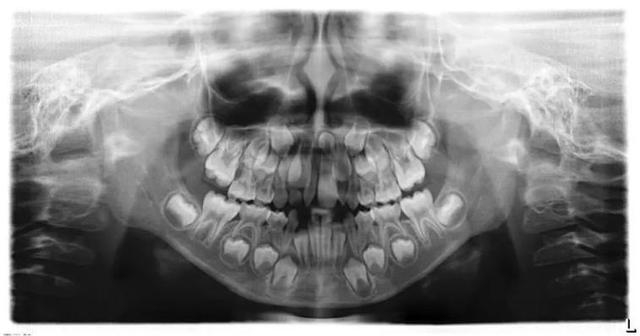

我们先给小朋友拍个全景片看一下是不是有多生牙吧。

医生,我们片子拍好了,有问题吗?

小朋友家长,这是刚拍好的片子,请看这个地方,是因为长了多生牙才影响了正常恒牙的位置,导致两颗牙齿之间的间隙过大。